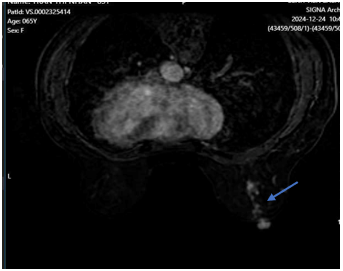

- Cộng hưởng từ tuyến vú có tiêm tương phản:

Hình 6. Hình ảnh cộng hưởng từ tuyến vú có tiêm tương phản: Hiện không thấy tổn thương nghi ngờ ác tính trên phim cộng hưởng từ tuyến vú hay bên/ Sau điều trị có đáp ứng hoàn toàn.

Nhận xét: Sau điều trị 6 đợt hóa chất tân bổ trợ phác đồ TCH, bệnh nhân lâm sàng ổn định, đáp ứng trên phim cộng hưởng từ vú có tiêm tương phản và trên phim cắt lớp vi tính lồng ngực. Đánh giá đáp ứng hoàn toàn theo tiêu chuẩn RECIST 1.1.